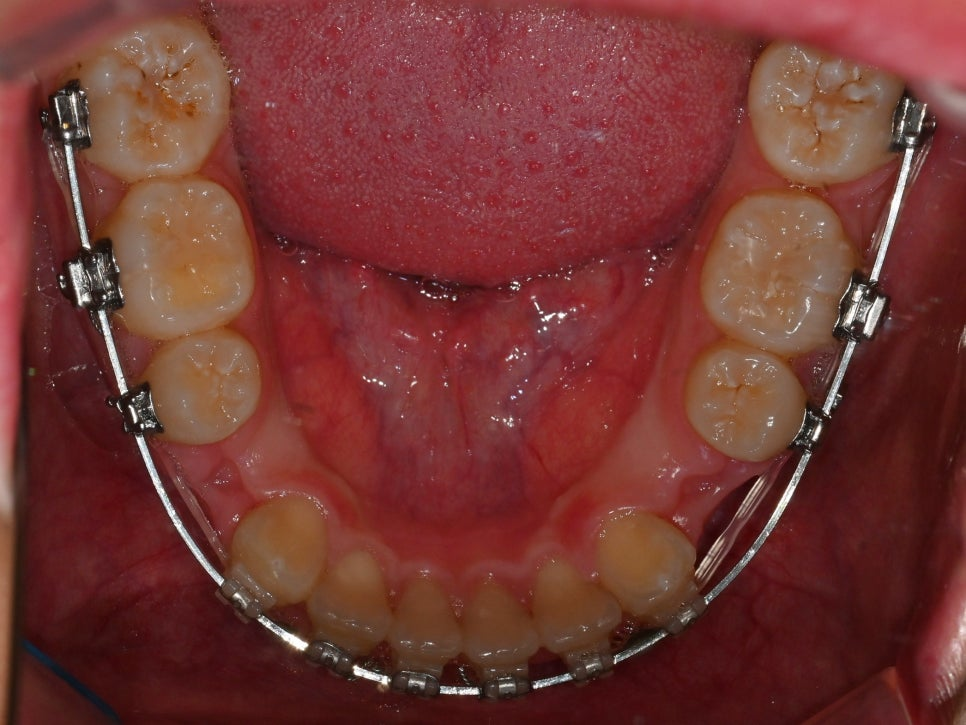

[사랑니 이동]

24.05.01

손상된 어금니 대신

건강한 사랑니를 앞쪽으로 이동시켜

어금니 역할을 하도록 하는 과정입니다.

이는 임플란트나 브릿지 없이도

자연치만으로

문제를 해결할 수 있습니다.